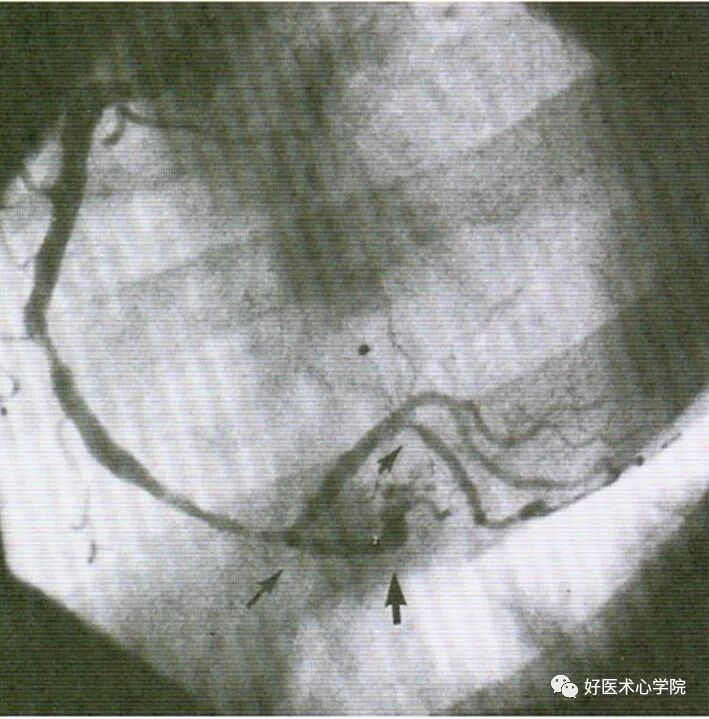

9. 侧支循环(Collateral Circulation)

当冠状动脉严重狭窄或阻塞时,近端灌注压明显下降,刺激侧支循环形成,血管远端被侧支循环逆向供血而显影。

造影导丝是什么珍藏 冠脉造影从流程到诊断,基础必备!_https://www.jmylbn.com_新闻资讯_第96张

侧枝:右冠脉→左前降支